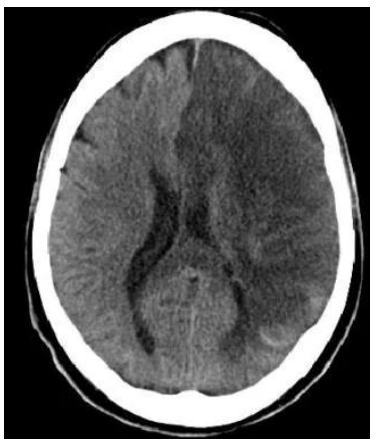

Paciente feminina de 57 anos, hipertensa e diabética tipo 2

insulino-dependente com tratamento irregular, admitida no

pronto socorro há 36 horas por acidente vascular encefálico

isquêmico em topografia de artéria cerebral média esquerda, fora

de tempo de trombólise.

Durante o seu plantão, a paciente evolui com rebaixamento do

nível de consciência e é entubada para proteção de vias aéreas. Ao

exame físico pós-intubação, encontra-se em RASS -5 sem

sedoanalgesia contínua, com anisocoria esquerda > direita,

mantendo hemiplegia dimidiada à direita, pressão arterial de

200x120 mmHg, FC de 65 bpm, ventilando em modo controlado,

bem acoplado e sem assincronias, com ausculta cardíaca e

pulmonar sem alterações.

Tomografia computadorizada de crânio sem contraste, com

hipodensidade fronto-parieto-temporal volumosa à esquerda,

apagamento de sulcos e desvio contralateral da linha média.